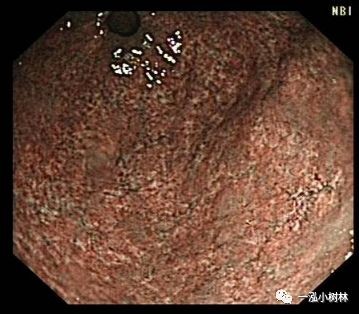

萎缩性胃炎是Hp感染胃黏膜中一种特征性胃炎。胃黏膜萎缩、肠上皮化生是发生分化型胃癌的背景。分化型胃癌发生的基本过程:正常胃黏膜——浅表性胃炎--萎缩性胃炎--肠化生-不典型增生--分化型胃癌。认识萎缩性胃炎、肠上皮化生对一个内镜医师至关重要。

萎缩性胃炎普通内镜表现:黏膜苍白,黏膜下血管透见,黏膜皱襞细小或消失,病变黏膜粗糙呈颗粒状或结节状,伴有肠化时轻者常不可见,重者可见斑片状、点状米粒大小白色或灰白色隆起改变,另外萎缩黏膜与正常黏膜可见到萎缩边界。

NBI+ME内镜表现:萎缩区域NBI放大可见胃小凹消失或不清晰,树枝状血管显露,黏膜苍白及萎缩边界更明显,多以幽门胃窦部为中心,随着萎缩的加重,胃体黏膜也散见,肠化区域可见胃小凹呈绒毛状,可见到“亮蓝嵴”“白色不透明物质”征。

例1

男性,56岁,萎缩性胃炎+肠化+Hp感染